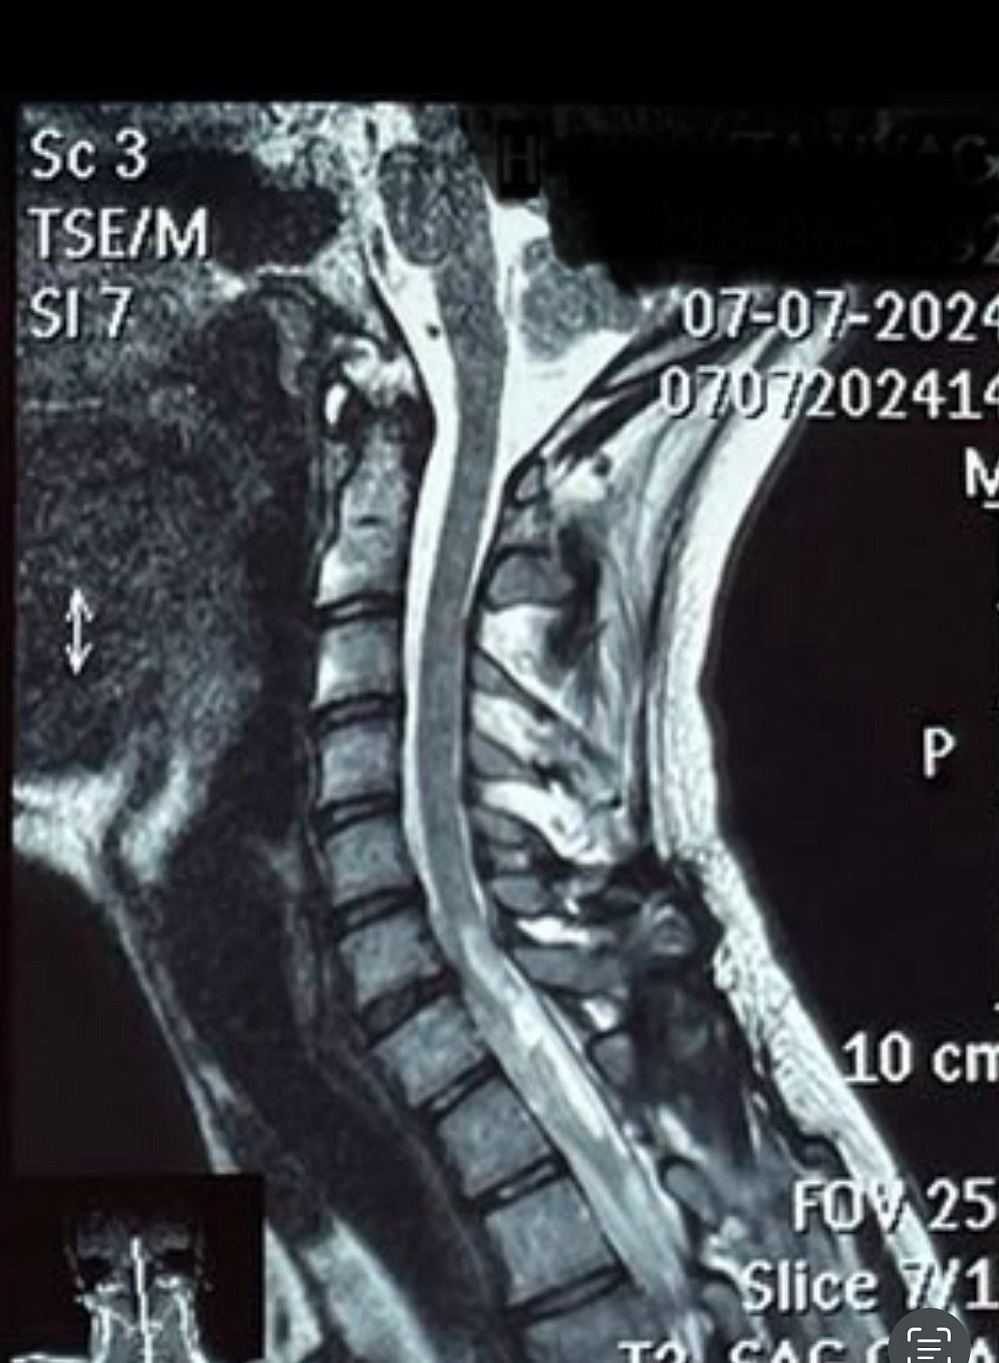

Як ви думаєте, про що ці фігурки, створені руками тяжкопораненого захисника України з вогнепальним ушкодженням шийного відділу хребта і спинного мозку?